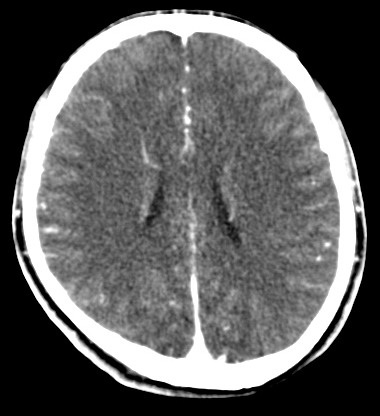

男,31岁,头疼就诊,其他不祥。

考虑右颞叶脑血管畸形伴出血。avm可能大,建议dsa。

平扫见右颞叶、右侧脑室后角旁略高密度影,增强未见明显病灶,基本正常。不放心做mri检查

病灶呈略高密度,周围伴环形水肿,无强化/无异常av影........

考虑为:1.脑内小血肿?   2.脑灰质异位?   建议mri检查........

考虑右颞叶脑血管畸形伴出血。考虑静脉血管瘤,深部型的,avm不除外,建议dsa。